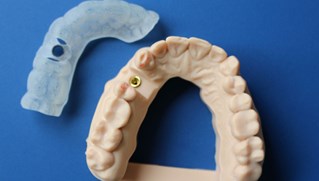

Inför operationen framställs en guideskena som underlättar operationen och ger oss en stor precision vid placeringen av titanskruven (fixturen)

Kronan kan antingen monteras som på bilden med en centrumskruv alternativt cementeras fast på en distans.